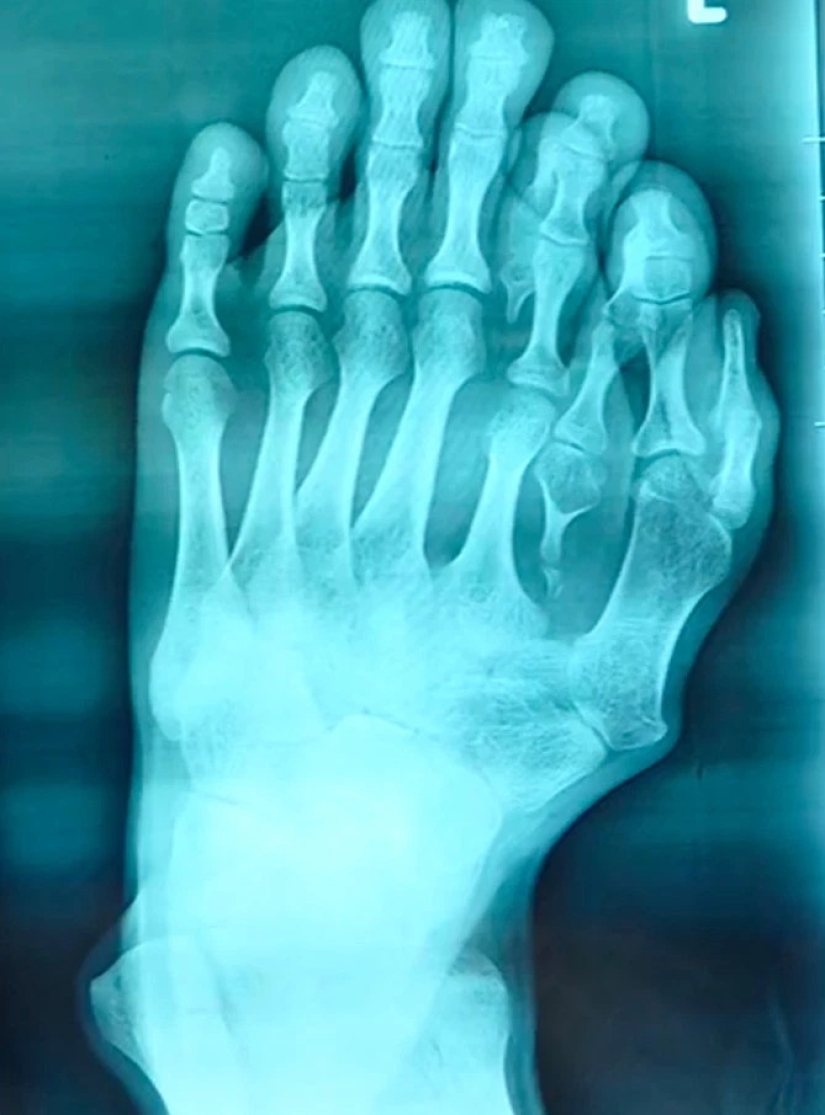

Por Pictolic https://www.pictolic.com/es/article/la-felicidad-nunca-es-demasiado-los-chinos-han-vivido-mucho-tiempo-con-14-de-los-dedos-de-los-pies-teniendo-en-cuenta-la-anomala-de-feliz-signo.htmlEl hombre que nació con cuatro dedos adicionales en la pierna izquierda, y el pensamiento acerca de la cirugía para deshacerse de ellos, porque sus padres creían que esta anomalía signo de buena suerte. Sólo recientemente, de 21 años, hombre Chino fue operado, dando la posibilidad de usar zapatos y encontrar la felicidad en su vida personal. Averiguar cómo el chico vivía con un poco de desviación de nuestro artículo.

Los padres de 21 años, China por el nombre de Azzun cree que cuatro dedos adicionales en mi pie izquierdo, el hijo, es un signo de buena fortuna. Los jóvenes anomalía trajo un montón de molestias en la vida cotidiana, así como el sufrimiento físico: en diez años se dejaron de usar sandalias porque el sangrado de las heridas en sus piernas.

Azzouni no es el único Chino con dedos adicionales. Tres meses bebé llamado JonJon — el propietario, de 15 de dedos y 16 de los dedos de los pies. Además, sus dos manos en cada mano, pero no los pulgares.